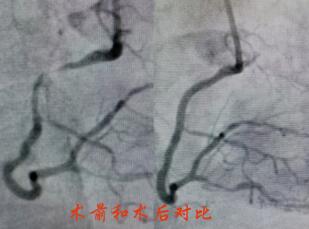

春節(jié)剛過(guò),陶奶奶的孩子們帶著陶奶奶再次來(lái)到了江寧中醫(yī)院心內(nèi)科準(zhǔn)備拆除這顆潛在的“致命炸彈”。韋鋒主任反復(fù)研究陶奶奶的前期手術(shù)影像,心中擬定著多個(gè)手術(shù)方案。經(jīng)過(guò)充分準(zhǔn)備,2月15日,韋鋒主任再次為陶奶奶進(jìn)行了介入手術(shù)。術(shù)中通過(guò)血管內(nèi)超聲(IVUS)精細(xì)、準(zhǔn)確評(píng)估陶奶奶的冠脈病變情況,發(fā)現(xiàn)陶奶奶的左主干最小管腔面積僅僅3.7mm2,;前降支近段全程鈣化,最嚴(yán)重處呈270度的環(huán)形鈣化,最小管腔面積僅僅2.1mm2;回旋支開(kāi)口正常,回旋支近端最小管腔面積1.8mm2。韋鋒主任根據(jù)IVUS的結(jié)果,改變了原來(lái)擬定的DKCRUSH術(shù)式,決定采用藥物球囊和藥物涂層支架相結(jié)合的方式處理病變(LCX藥物球囊,LM-LAD植入支架),經(jīng)過(guò)近2個(gè)小時(shí)的手術(shù),陶奶奶的冠脈血管又“完美”地回來(lái)了。

韋鋒主任術(shù)中在仔細(xì)研究陶奶奶的IVUS結(jié)果,指導(dǎo)手術(shù)更精確的進(jìn)行。